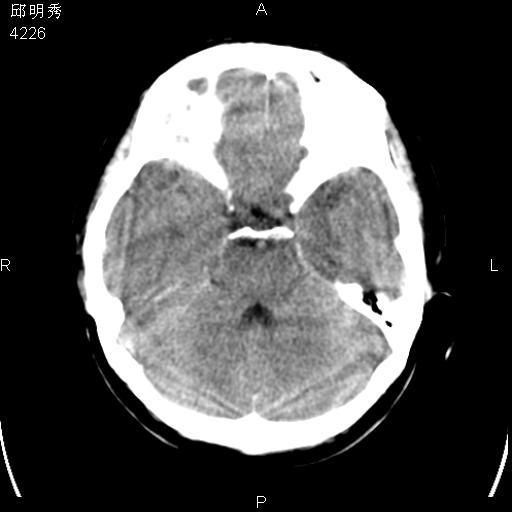

40f头晕十多天,右上肢麻木一天

脑白质变性或ms

脑白质脱髓鞘改变。

脑白质病;建议行mri检查。